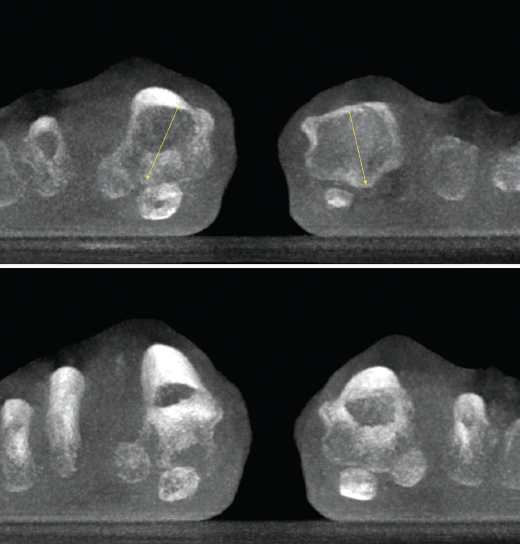

Figura 3. Inestabilidad franca de la columna medial en pie plano.

- Pie plano valgo del adulto. Permite la valoración de la articulación subtalar, el valgo del retropié y la inestabilidad de la columna medial (Figuras 2 y 3).

- Inestabilidad de la columna medial o inestabilidad tarsometatarsiana. Valoración y estudio de la columna medial en carga (Figuras 5 y 6).